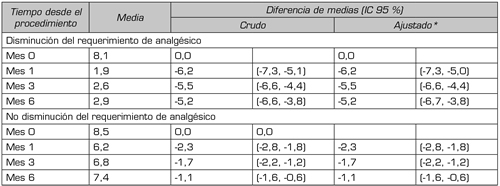

La Tabla 2 presenta el cambio medio en el dolor percibido relacionado con la disminución del requerimiento de analgésicos. En el 20 % de los pacientes que disminuyeron el requerimiento de analgésicos, la media de dolor en la línea de base fue de 8,1 puntos en la EVA; a un mes de la intervención mostraron descenso de 6,2 puntos (IC 95 %; -7,3, -5,0). Al sexto mes la diferencia de medias se redujo en aproximadamente un punto, manteniéndose estadísticamente significativa (-5,2; IC 95 %: -6,7, -3,8). En el 80 % de los pacientes que no tuvieron disminución de requerimiento de analgésicos, la media al primer mes fue de 2,3 puntos (IC 95 %: -2,8, -1,8) cerrándose para el sexto mes en 1,1 puntos (IC 95 %: -1,6, -0,6). En la Figura 1 se observan las diferencias de medias entre los meses 1, 3 y 6, siendo estadísticamente significativas solo en el último control. Estas diferencias no son explicadas por la edad, sexo o nivel socioeconómico de los pacientes.

Tabla II. Disminución media del dolor a los 1, 3 y 6 meses del procedimiento, según disminución en el requerimiento de analgésicos.

*: Ajustado por edad, sexo y nivel socioeconómico.